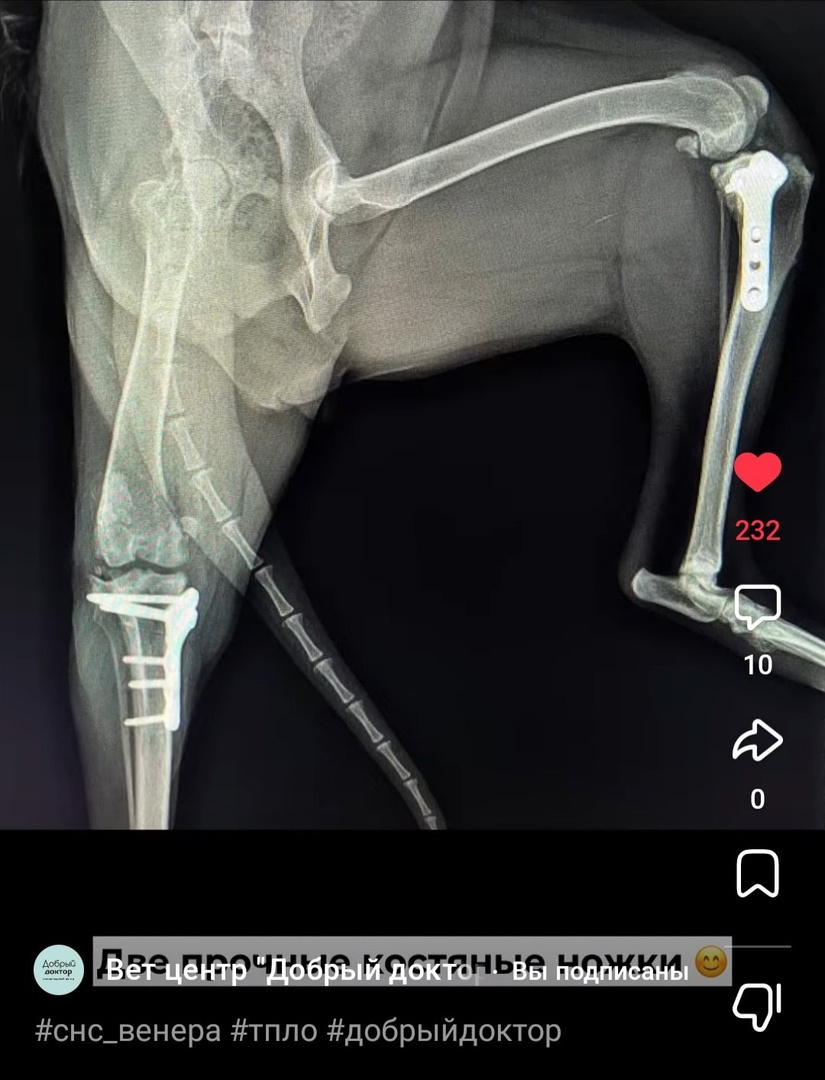

В этом году ей были проведены операции на связках обеих лап, вставлены пластины,

Венера, собака после операции. Оплата теплой передержки до весны